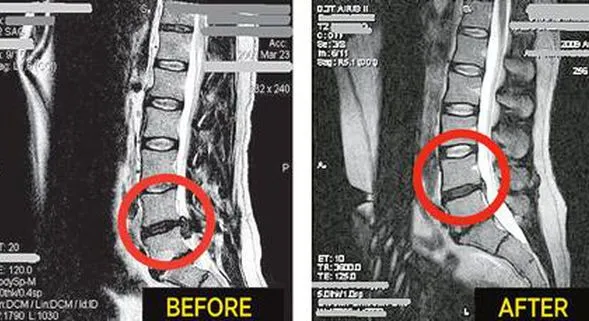

This FDA-approved technology relieves pain by enlarging the

space between the discs.

Patients who suffer from chronic neck or low back pain associated with bulging or herniated discs, Degenerative Disc Disease, Facet Syndrome, Spinal Stenosis, Pre/Post-surgical Pain Syndrome, and other serious spinal related conditions find increased benefits from treatments immediately after using our spinal decompression table.

According to a clinical study performed by the Orthopedic Technological Review in 2004, said that 86% of all cases experienced spinal pain relief with disc decompression.